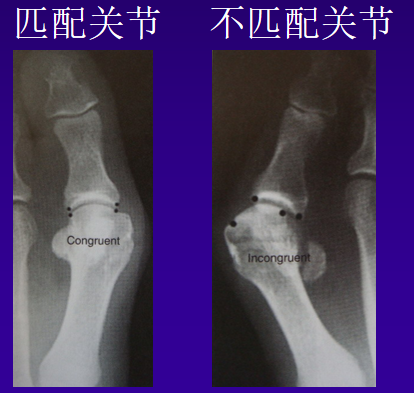

关节面匹配情况

适应症:关节面匹配矫正严重的远端关节角矫正拇指外展

适合关节:骨性手术不适合关节:加软组织手术关节炎

适合关节

软组织手术:IMA<12Chevron截骨:12 < IMA<15跖骨干或远端截骨:15<IMA<20Lapidus:IMA>20Akin截骨:矫正严重的远端关节角

不适合关节

IMA<13,HAV<30: Chevron截骨+软性手术IMA>13,HAV<40:跖骨干或远端截骨IMA>20,HAV>40:跖骨远端截骨或lapidus术跖楔关节松弛:lapidus术